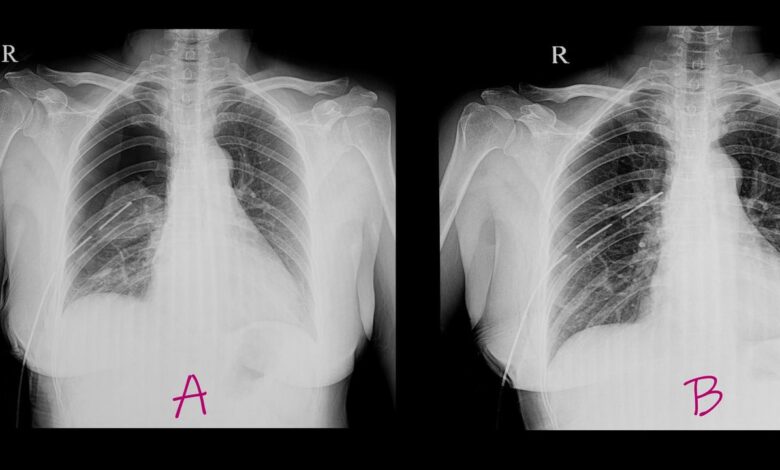

El colapso pulmonar o neumotórax ocurre cuando el aire se filtra en el espacio entre los pulmones y la pared torácica, lo que impide que el pulmón se expanda completamente. De acuerdo con la clínica Mayo, los síntomas incluyen un dolor de pecho repentino y la falta de aire, aunque la gravedad dependerá del nivel del colapso pulmonar. Puede ocurrir espontáneamente en personas jóvenes y fumadoras, por un trauma, por tejido pulmonar dañado, o como resultado del síndrome BHD.